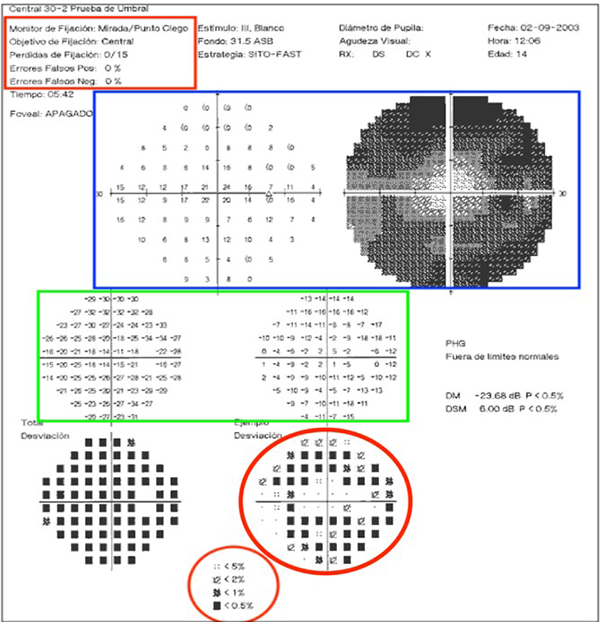

Figura 1: Interpretación de campo visual. Rojo: Fiabilidad; Azul: Mapa colorimétrico y numérico; Verde: Desviación total; Círculo: Defecto poblacional.

Interpretación de campimetría visual computada.

Lo primero que debemos saber es que ojo se está evaluando. Siempre se encuentra especificado como OS (ojo siniestro o izquierdo) u OD (ojo derecho). Luego debemos interpretar si esta prueba es fiable o no. Esto se realiza con los denominados índices de fiabilidad: falsos positivos, falsos negativos, y pérdida de fijación. La presencia de >20% falsos positivos o negativos, y/o la pérdida de al menos 3 puntos de fijación es recomendación de repetir la prueba ya que se puede considerar no fiable (Figura 1, apartado rojo).

Una vez que la prueba es fiable se continúa con la interpretación de los dos gráficos inferiores. Vamos a encontrarnos con uno numérico y otro en escala de grises. Este último es el más fácil de interpretar y es útil en el seguimiento del paciente. A cada punto evaluado se le otorga un determinado valor de sensibilidad al que a su vez (a diferencia del mapa numérico) se le otorga un color. Cuanto más sensible, más claro el color asignado. El inconveniente con este gráfico es que se puede pasar por alto la variación en la línea de tiempo, ya que la asignación de colores a veces suele ser muy similar. Por dicho motivo, una vez que hemos visualizado el tipo de defecto y la topografía, se recomienda pasar al mapa numérico donde se puede comparar punto por punto (fig. 1, apartado azul).

Los siguientes gráficos son mapas numéricos diferenciales que comparan el examen del paciente con los valores normalizados para su edad (mapa de desviación total) (fig. 1, apartado verde).

En los últimos mapas se va a ver representada la probabilidad estadística de dicha alteración en la población general. Por ende, si encontramos P<5%, significa que la probabilidad de encontrar dicho defecto es menor al 5% (fig. 1, apartado circular).

Figura 1: Interpretación de campo visual. Rojo: Fiabilidad; Azul: Mapa colorimétrico y numérico; Verde: Desviación total; Círculo: Defecto poblacional.